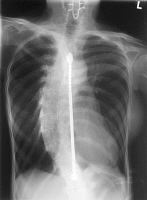

Refer to the picture above for question 5

5. Associated features for the above condition include :